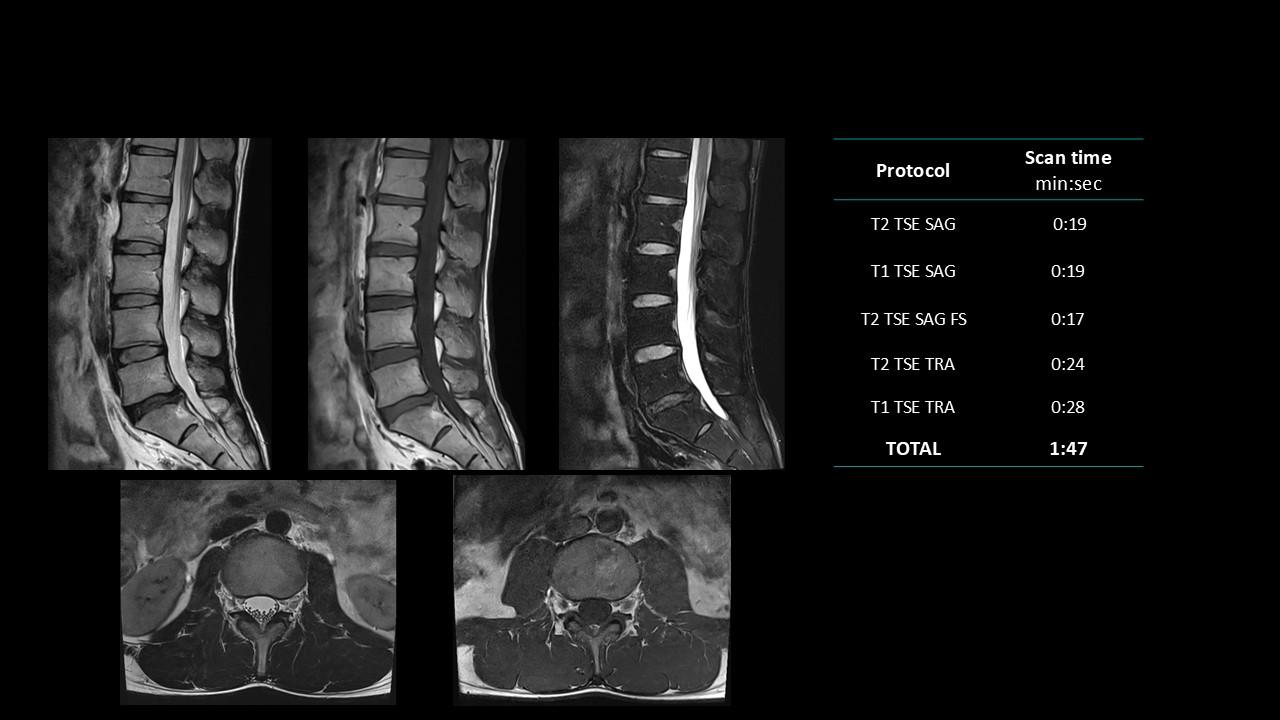

The Deep Resolve protocols are a set of advanced 3T MR imaging protocols designed to achieve high-quality diagnostic imaging with significantly reduced acquisition times.

Enabled by Deep Resolve, the AI-powered image reconstruction technology, these protocols deliver high-quality scans in approximately three minutes across a wide range of anatomical regions.

Developed and meticulously evaluated by Dr. Seong-ho Lee of Leaders Radiology Hospital in Seoul, Korea, the protocols integrate deep learning technology to enhance imaging efficiency while maintaining diagnostic detail.

By reducing scan duration, they improve workflow efficiency and patient experience without compromising image quality.